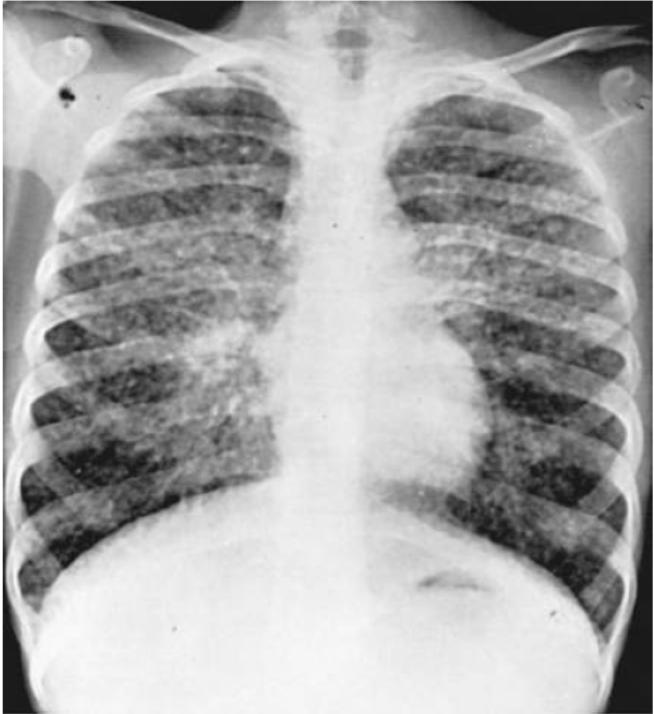

因疑诊结节病而接受评估的所有患者均应行胸片检查。双侧肺门淋巴结肿大是结节病的典型表现,肺门可能对称性增大(在约50%的病例中)或右侧稍更显著。真正的单侧淋巴结肿大并不常见(<5%的病例)。肺实质表现更为多样,可为正常、弥漫性网状影或磨玻璃样不透光区、结节性实变或囊性瘢痕形成。

现已根据胸部X线摄影表现对肺部受累进行分期,尽管这能提示肺部受累的解剖学情况,但并不能反映疾病活动度或功能受损程度。

10岁女孩的结节病胸片:多发性细结节伴有肺门淋巴结肿大